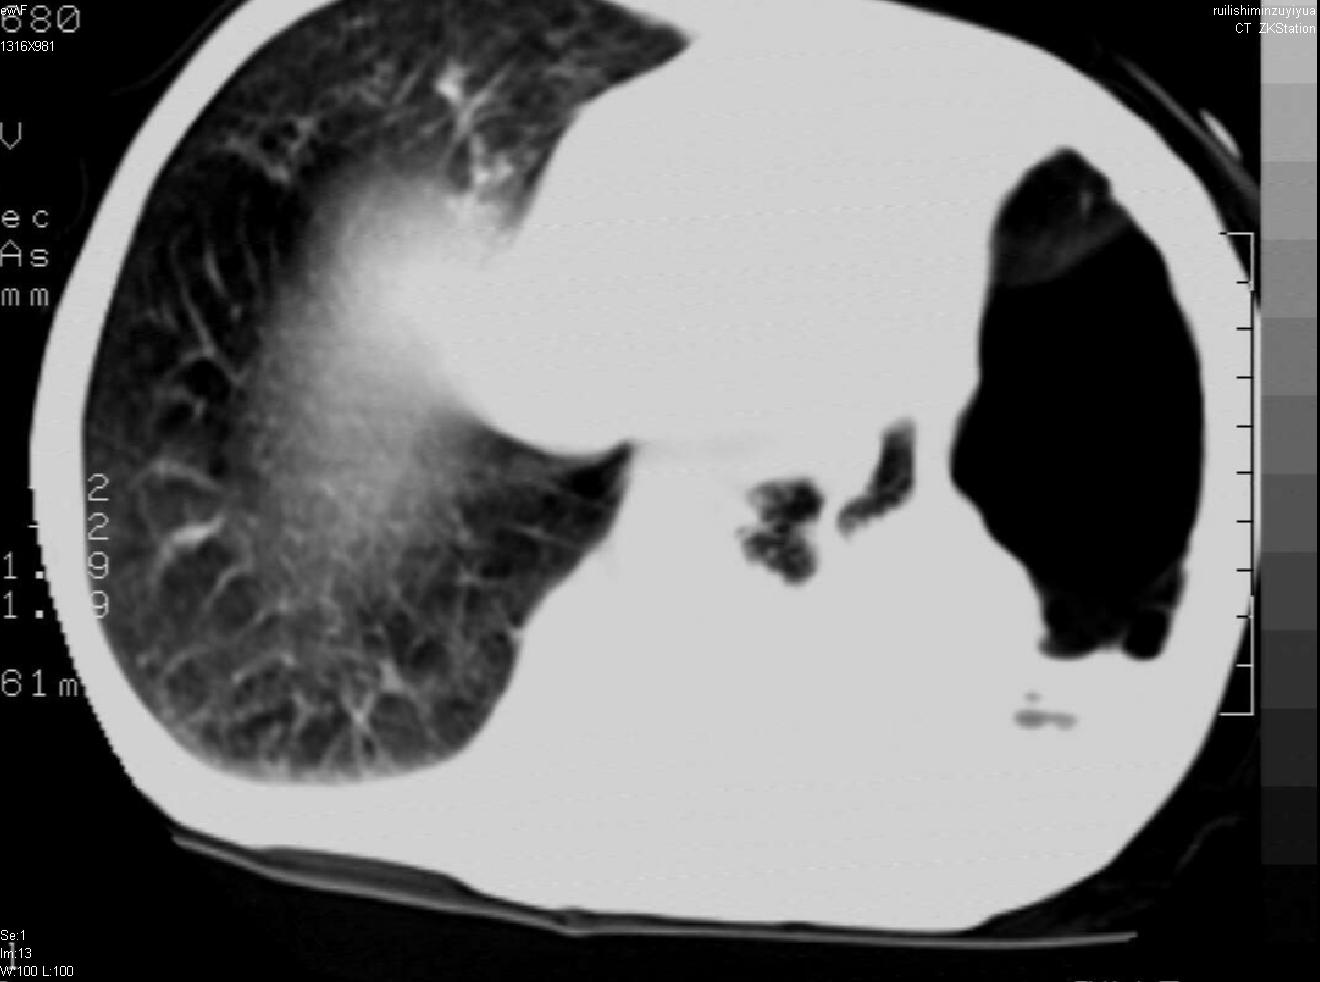

以下是引用天南地北在2007-6-11 23:32:00的发言:[br]1:左侧肺毁损(结核性)伴感染(多发空洞伴液平面)。[br]2:右肺继发型肺结核。

以下是引用avril在2007-6-12 1:17:00的发言:[br]1、左肺毁损。[br]2、左肺多发肺大泡伴自发性气液胸形成。[br]3、右肺继发型结核。

以下是引用尚峰在2007-6-11 22:44:00的发言:[br]慢阻肺、肺纤维化、肺大泡、气胸形成,此患者有没有急性病史?